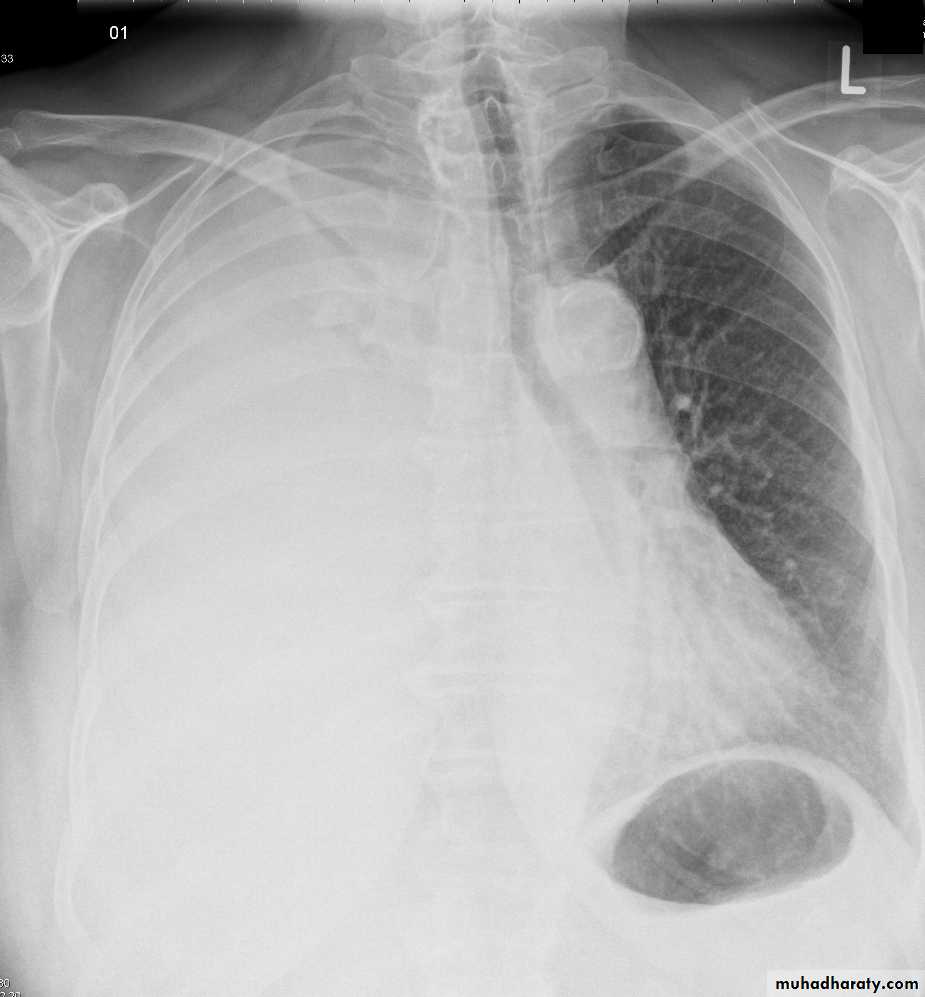

Chest X ray: The pleural fluid accumulates in the most dependent part of the thoracic cavity

The normally sharp posterior costophrenic angle is obliterated.

Upper surface is meniscus-shaped (meniscus sign).

Around 200 mL of fluid is required in order for it to be detectable

on a PA chest X-ray

The amount of pleural effusion may be small, large or massive.

Plueral malignancyPrimary: Mesothelioma is a malignant tumour affecting the pleura (pleural mesothelioma) or, less commonly, the peritoneum (peritoneal mesothelioma) due to asbestos exposure. It has poor prognosis.

Secondary : metastasis involving the pleura with malignant effusion is more common cause than primary one.

Malignant mesothelioma